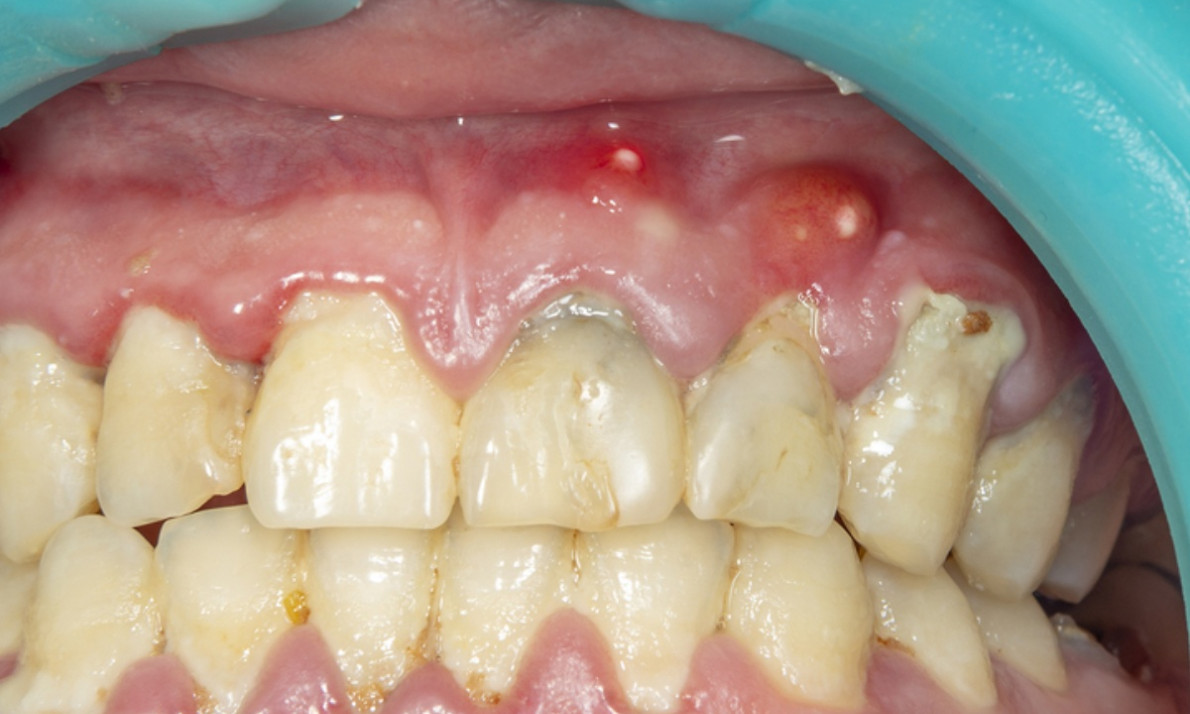

Η συγκέντρωση πύου στα ούλα ή στη ρίζα του δοντιού, που οφείλεται στην ύπαρξη φλεγμονής, ονομάζεται απόστημα.

Τα αποστήματα εμφανίζονται συνήθως μετά από οδοντιατρική χειρουργική επέμβαση, εξαιτίας λοίμωξης των ούλων, τραυματισμού ή φθοράς των δοντιών.